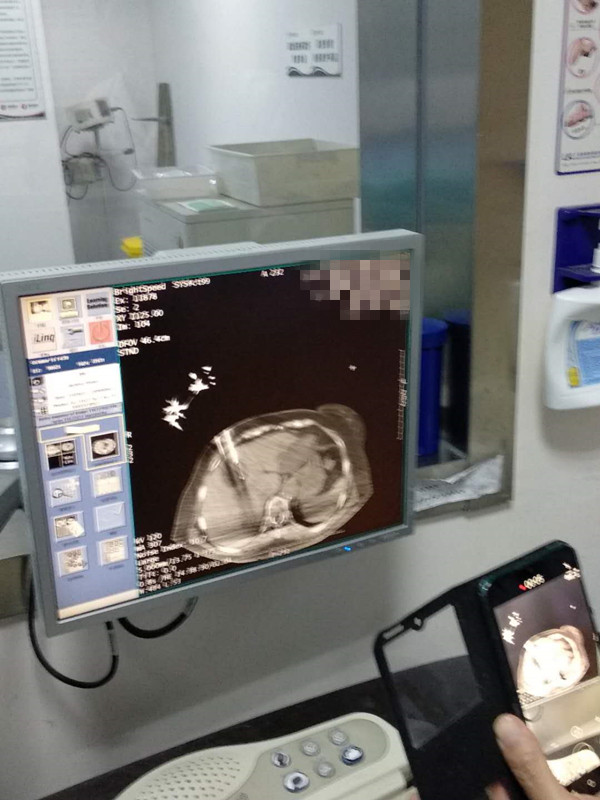

73岁患者肝部氩氦刀冷冻消融

发布人:美国氩氦刀技术官方网站    发布时间:2020/10/16 16:15:21